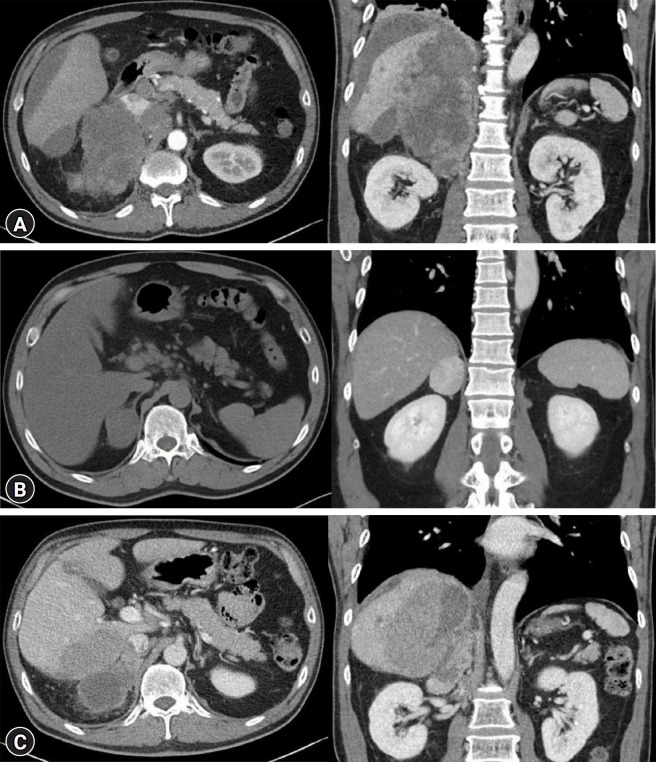

我们报告了一例三重激素分泌型肾上腺肿块破裂病例,患者伴有高醛固酮血症、高皮质醇血症和正常肾上腺素水平升高,经组织学诊断为肾上腺皮质癌(ACC)。一名 53 岁的男性患者最初因腹痛被转诊至我院,接受肾上腺肿块破裂血管凝固术。腹部计算机断层扫描显示,患者右侧肾上腺有一个 19×11×15 厘米的异型肿块,肿块侵犯肝右叶、下腔静脉、后腔淋巴结和主动脉淋巴结。患者接受了血管凝固治疗。实验室评估显示,1 毫克过夜地塞米松抑制试验阳性,皮质醇过多;生理盐水输注试验阳性,原发性醛固酮过多症;血浆去甲肾上腺素水平高于正常值三倍。由于考虑到肿瘤的范围,手术治疗并不合适,因此患者接受了肾上腺肿块活检进行病理确认,以便开始姑息化疗。病理检查显示患者为 T4N1M1 期 ACC。患者开始了第一周期的米托坦辅助治疗以及多柔比星、顺铂和依托泊苷的辅助治疗,随后出院。皮质醇和醛固酮双重分泌型 ACC 或 ACC 表现为嗜铬细胞瘤的临床病例偶有报道,但这两种情况都很少见。此外,据我们所知,还没有关于三重激素分泌型 ACC 的报道。在此,我们报告了一例罕见病例及其治疗方法。本病例报告强调了对肾上腺肿块患者进行全面的临床和生化激素评估的必要性,因为 ACC 可表现为多种激素升高。

We report a case of a ruptured triple hormone-secreting adrenal mass with hyperaldosteronism, hypercortisolism, and elevated normetanephrine levels, diagnosed as adrenal cortical carcinoma (ACC) by histology. A 53-year-old male patient who initially presented with abdominal pain was referred to our hospital for angiocoagulation of an adrenal mass rupture. Abdominal computed tomography revealed a heterogeneous 19×11×15 cm right adrenal mass with invasion into the right lobe of the liver, inferior vena cava, retrocaval lymph nodes, and aortocaval lymph nodes. Angiocoagulation was performed. Laboratory evaluation revealed excess cortisol via a positive 1-mg overnight dexamethasone suppression test, primary hyperaldosteronism via a positive saline infusion test, and plasma normetanephrine levels three times higher than normal. An adrenal mass biopsy was performed for pathological confirmation to commence palliative chemotherapy because surgical management was not deemed appropriate considering the extent of the tumor. Pathological examination revealed stage T4N1M1 ACC. The patient started the first cycle of adjuvant mitotane therapy along with adjuvant treatment with doxorubicin, cisplatin, and etoposide, and was discharged. Clinical cases of dual cortisol- and aldosterone-secreting ACCs or ACCs presenting as pheochromocytomas have occasionally been reported; however, both are rare. Moreover, to the best of our knowledge, a triple hormone-secreting ACC has not yet been reported. Here, we report a rare case and its management. This case report underscores the necessity of performing comprehensive clinical and biochemical hormone evaluations in patients with adrenal masses because ACC can present with multiple hormone elevations.